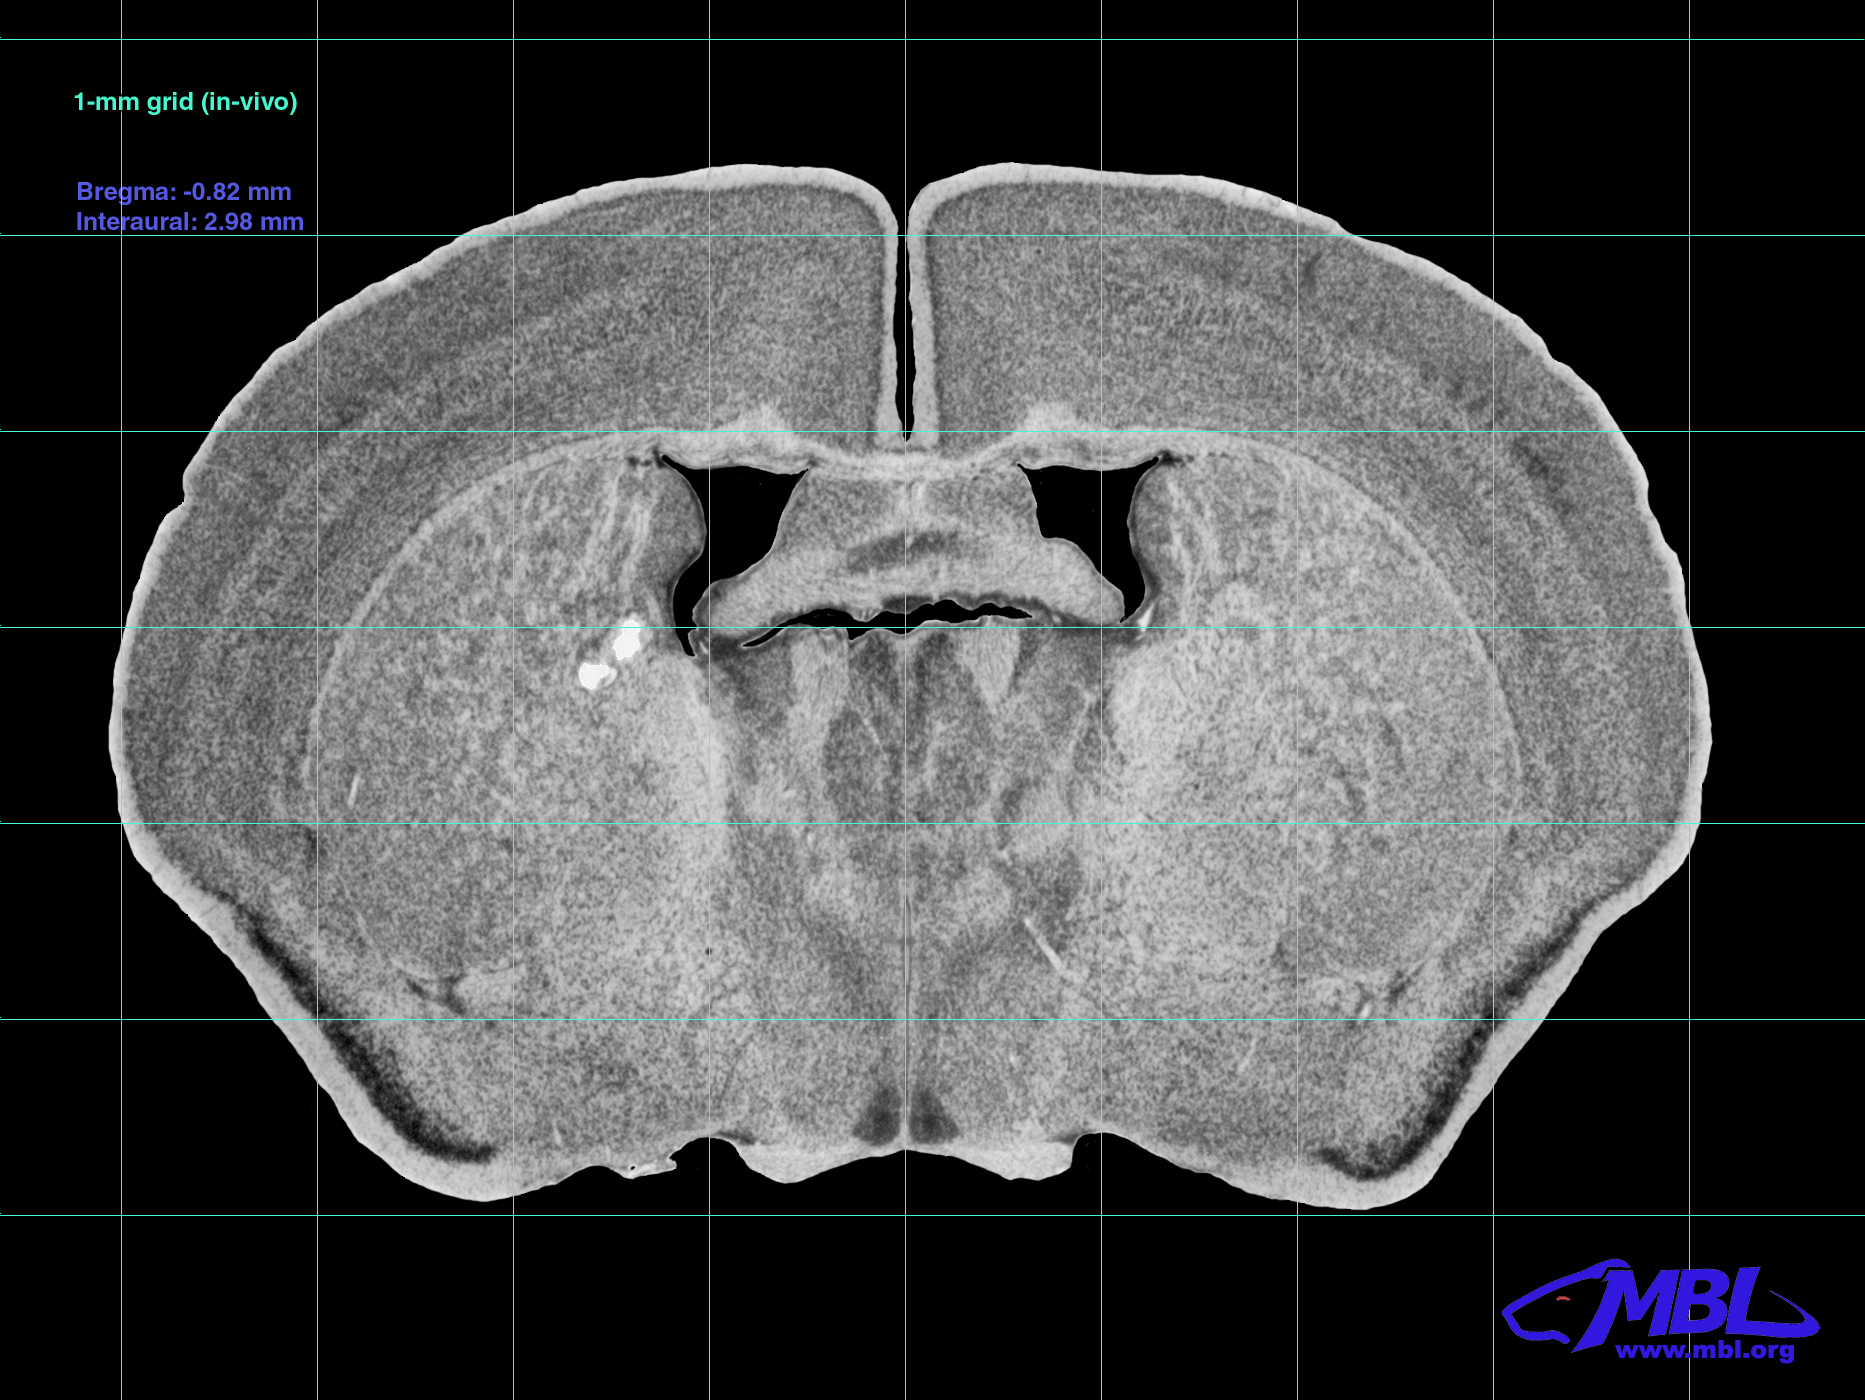

C57BL/6J Atlas - Section 17

Interaural: 2.98 mm

Bregma: -0.82 mm

Mouse Brain Section